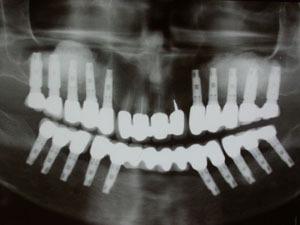

מקרה 1:

שתלים ותותבות על שתלים

מקרה 2:

תותבות על שתלים עם מחברים כדוריים או לוקייטורים

מקרה 3:

תותבות על שתלים

מקרה 4:

צילום של בר

בר שתומך בתותבת נתמכת שתלים